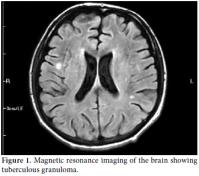

A 22-year-old male patient was presented to the emergency room of our hospital with complaints of fever, headache, and fatigue which had been occurring for 10 days. The medical history revealed that he had been diagnosed as having Behçet’s disease in 2007 and had been using prednisolone since the time of diagnosis. The dosage of prednisolone was increased up to 64 mg/day by the supervising clinician. Cyclosporine-A had been added to the treatment at 100 mg/day two months previously due to eye involvement but was discontinued after one week due to side effects of fever, fatigue, and headache. The patient was prescribed azathioprine at 100 mg/day on the follow-up visit, and he had been using this drug for nearly 10 days prior to being admitted to our hospital. The physical examination findings revealed a body temperature of 39.8 °C, arterial blood pressure of 110/70 mmHg, and a heart rate of 112/per minute. Neck stiffness was minimally positive. He had swelling and sensitivity on palpation in the right scrotal region that had started three months earlier. Laboratory examinations were as follows: leukocyte count 7.400/mm3, erythrocyte sedimentation rate 87 mm/h, C-reactive protein: 13.4 mg/dl in cerebrospinal fluid (CSF) analysis, leukocyte count: 20/mm3, protein: 200 mg/dL, and glucose: 27 mg/dL (blood glucose: 94 mg/dL). There was no growth on the CSF culture. A chest X-ray was normal. Since the CSF findings and physical examination results could not rule out bacterial meningitis, he was started on ceftriaxone 2x2 gr intravenously. He had no regression of complaints in the first week of treatment, and his antibiotic treatment was discontinued. Internal disease and neurology consultations in conjunction with the clinical findings and CSF results led to a diagnosis of neuro-Behçet’s disease. Scrotal ultrasound screening was consistent with epididymitis. A large number of leukocytes were observed in the material aspirated from the testis (90% lymphocyte in nature). Ehrlich- Ziehl-Neelsen (EZN) staining detected acid-resistant bacteria. Treatment with isoniazid, ethambutol, pyrazinamide, and rifampicin was initiated under the diagnosis of testis tuberculosis. Subsequently, chest high resolution computed tomography (HRCT) and brain magnetic resonance imaging (MRI) were done. The chest HRCT result was consistent with miliary tuberculosis (Figure 1), and the brain MRI revealed findings were consistent with tuberculous granuloma and tuberculous meningitis (Figure 2). The vertebral MRI showed that widespread lytic lesions in the vertebra corpuses and the tissue swelling adjacent to the vertebra were consistent with Pott’s disease and spinal granuloma (Figure 3a and 3b). Based on these examinations, the patient was considered to have disseminated tuberculosis (testicular tuberculosis, miliary tuberculosis, tuberculosis meningitis, spinal granuloma, and Pott’s disease). The anti-tuberculous treatment was revised with the ethambutol being replaced by streptomycin. The patient’s body temperature returned to normal on the eighth day of treatment. The patient, whose general condition was observed to improve, is still receiving the treatment.